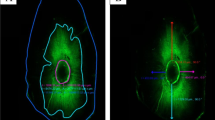

The prepared discs were stained using a Live and Dead Bacterial Viability kit (L-7012 Molecular Probes; Eugene, OR, USA), which consists of two separate vials of two-component dyes (propidium iodide and SYTO9 mixed 1:1) for staining the bacteria. The dyes had excitation/emission maxima of 490–635 nm for propidium iodide, which stained dead bacteria in red, and 480–500 nm for SYTO 9, which stained active bacteria in green [26]. Following staining, the specimens were examined by CLSM (Leica DMi8; Leica Microsystems CMS GmbH, Germany). Single-channel imaging was used to display green and red fluorescence separately, after which the two channels were merged using LAS X software (version 1.1.0.12420; Leica Microsystems CMS GmbH). CLSM images of the bacteria within infected dentinal tubules were captured at a resolution of 1024 × 1024 pixels, and the specimens were assessed using ×5 and ×10 lenses.

Descriptive analysis of Confocal Laser microscopic images

The CLSM (×5 and ×10 magnification) images revealed viable bacterial penetration in all the positive control group specimens by the green fluorescence. Meanwhile all the negative control group specimens showed no fluorescence because of the absolute absence of bacteria.

For the three experimental groups, the red fluorescence indicating dead bacteria was the prominent feature seen with no visible difference in the distribution of the dead bacteria. Although minute spots of green fluorescence where detected nearby the root canal lumen (Figs. 5 and 6).

(a-f): demonstrating images from confocal laser scanning microscopy (CLSM) (magnification scale; a: 0–500 μm, b–f: 0–250 μm), of the E.fecalis bacterial penetration into the dentinal tubules of experimental group specimens .Green displays live bacteria(f), red displays dead bacteria (e).The bacteria can be presented at high (b-f) and low magnification (a)